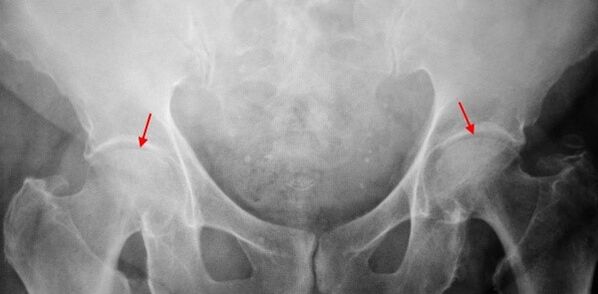

In the X -ray of the patient suffering from the 1 degree coxarthrosis, mild changes are determined: the uneven moderate narrowing of the joint gap, as well as the bone growth around the outer or inner edge of the acetabule in the absence of femur's head and neck changes.

In the X -Ray images for the 2nd degree coxarthrosis, the important uneven narrowing of the joint gap (more than half of the normal height) is determined.The femur's head is displaced somewhat up, deformed and increases in size, and its contours become uneven.Bone growths with this degree of coxarthrosis appear not only in the interior but also on the outer edge of the acetabulum and go out of the cartilage.

In radiographs for 3rd degree coxarthrosis, a sharp narrowing of the joint gap is detected, a pronounced expansion of the thigh head and numerous bone growth.

The diagnosis of coxarthrosis is based on clinical signs and data of additional studies, the main of which is radiography.In many cases, the X -rays make it possible to place not only the degree of coxarthrosis, but also the cause of its appearance.Thus, for example, an increase in the angle of the diaphysis in the neck, scenes and flattening of acetabulum indicate dysplasia, and changes in the form of the proximal femur part are shown that coxarthrosis is a consequence of God's disease or youth epiphysiolis.In radiographs of patients with coxarthrosis, changes can also be detected by indicating injuries.